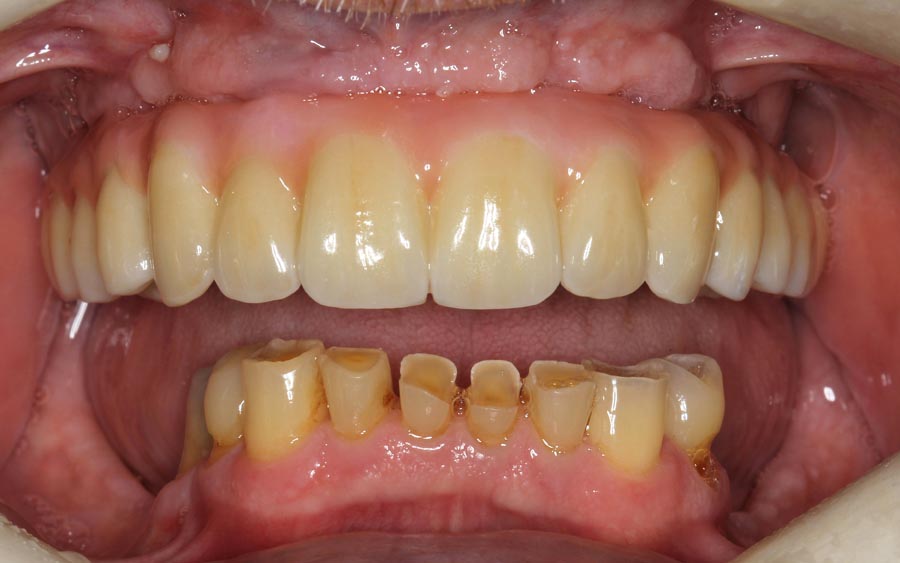

The lower teeth were bonded with composite resin to improve aesthetics and function during the year he is waiting to do his lower.

Smile of upper permanent and lower bonded teeth. The patient is starting to learn how to smile, again!

Final upper zirconium implant bridge. Final lower titanium/acrylic bridge. For patients with grinding habits, I recommend different materials in the opposing jaws to decrease the chances of breakage. Here, the lower acrylic teeth are softer than the upper zirconium which allows for tooth wear (attrition) instead of breakage.